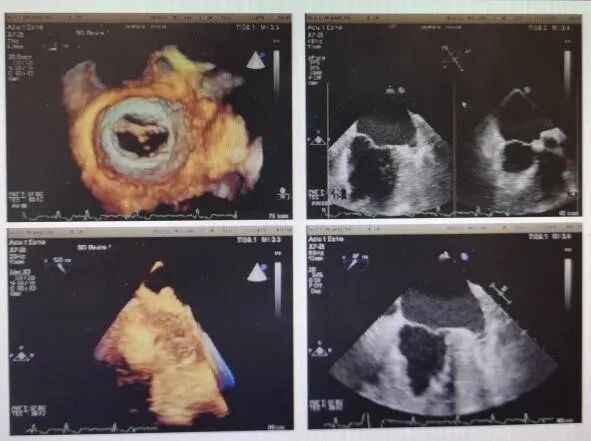

经胸心脏彩超示:主动脉瓣重度返流,缩流颈8.5mm,返流面积8.1cm²;左心扩大,左室舒张末内径66mm,左室收缩末内径40mm,左房45mm,EF62%。基于心脏CTA的评估显示患者为三叶主动脉瓣且无明显钙化,瓣环周长折算直径24.4mm,左冠开口高度9.8mm,左冠瓣瓣叶长度13.5mm,左髂总动脉瘤。NT-proBNP1991.0pg/ml,肌酐174.57umol/L。心电图、肺通气功能、胸片未见异常。

造影见主动脉瓣大量反流

瓣膜释放前经食道超声

该患者体表面积为1.86m²,STS PROM达8.68%。鉴于患者瓣为纯返流病变,且年龄较高、左冠瓣较长、手术风险大,在与患者及家属充分沟通后,郭惠明教授与刘健教授决定给患者行经心尖TAVR,选用27mm瓣膜。

瓣膜释放后食道超声